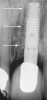

Fig 2. A periapical radiograph of an implant placed in the position of the maxillary left central incisor. The implant at mid-body was clinically confirmed to be in contact with the contents of the nasopalatine canal (arrow). This was validated by inserting a round-ended implant probe into the osteotomy before placing the implant and observing movement of the canal’s contents at the nasopalatine foramen. At the 4-year follow-up (not shown), the patient continued to be symptom free.

Figure 2